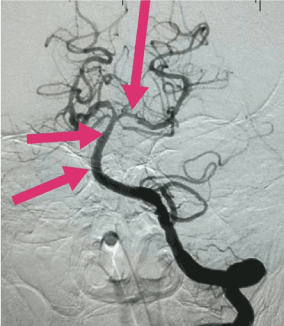

The patient was given a supine position before operation, and the anesthesia was determined according to the patient's degree of coordination. If the patient can cooperate, only local anesthesia is given. If the patient is in poor state of consciousness, it is easy to cooperate with the general anesthesia. Most patients adopt endovascular treatment under local anesthesia, using modified Seldinger technique puncture femoral artery on the right or the left femoral artery, in 6F arterial sheath pipe, using imaging tube first whole cerebral angiogram collateral compensatory situation of clear and to assess the lesion site. If blood vessel occlusion or subtotal occlusion is found and the indications are consistent with endovascular treatment indications, intravascular treatment is tried, as shown in Figure 2.

Figure 2. An occlusion of the distal end of the preoperative basilar artery